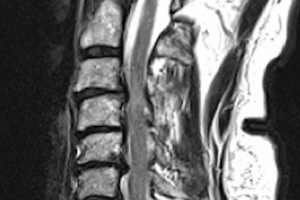

Cervical myelopathy is one of the most important spinal conditions to diagnose and treat in time. It occurs when the